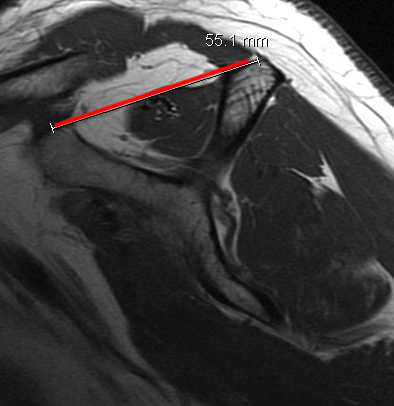

Tangent sign

- sagittal MRI

- line connecting superior coracoid and superior border scapular spine

- if supraspinatus muscle is below line, there is significant atrophy

- positive tangent sign / significant atrophy associated with larger tears / irrepairable tears

Negative tangent / no atrophy Positive tangent / significant supraspinatus atrophy